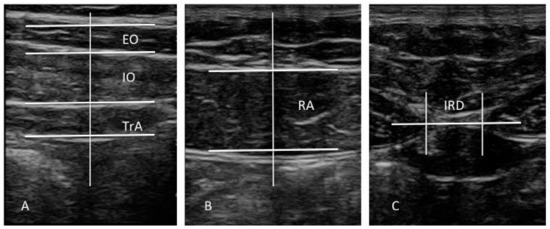

All evaluations were carried out by a single operator (J.A.P.), a specialized physical therapist with 3 years of RUSI experience. The evaluator was not blinded to both groups during data evaluation [12]. A diagnostic ultrasound tool (Toshiba Aplio 500 Platinum; Toshiba American Medical Systems, Tustin, CA, USA) with a 7–14 MHz range linear transducer (18L7 PLT-1204BT type; 40 mm footprint) was used for B mode ultrasound imaging. According to the protocol of Whittaker et al. [12], ultrasound images of the EO, IO, and TrAb muscles were carried out with the subjects in supine position, with a cross-reference point placed between the iliac crest and the inferior border of subcostal line and the midaxillary line (Figure 1A and Figure 2A); RA muscle was aligned with the umbilicus (Figure 1B and Figure 2B); and IRD was measured just under the umbilicus (Figure 1C and Figure 2C). Previously, anatomical landmarks were located by means of palpation and a dynamic ultrasound evaluation following the methodology proposed by Whittaker et al. [12], which showed excellent interday and interexaminer reliability (ICC = 0.92–0.99) for these RUSI measurements. The mean of 3 repeated values was collected for each measurement at the end of expiration, maintaining the transducer at the same point and with the same pressure (only the pressure generated by the weight of the transducer). IRD was only evaluated in the midline. The rest of the measurements were obtained at the left and right sides. Muscle thickness was measured at the center on the image and considered as the distance (cm) between the inside caliper lines of each muscle border. EO thickness was perpendicularly measured inside the superficial connective tissue and the connective tissue located between EO and IO. IO thickness was perpendicularly measured inside the connective tissue located between EO and IO and between IO and TrAb. TrAb thickness was perpendicularly measured inside the deep connective tissue and the connective tissue located between IO and TrAb (Figure 2A). RA thickness was perpendicularly measured inside the superficial and deep connective tissues (Figure 2B). IRD was described as the horizontal distance between both RA muscles (Figure 2C) [12]. ImageJ software (version 2.0; US National Institutes of Health, Bethesda, MD, USA) was employed to measure all the images offline [28].

Figure 1.

Transducer placement during ultrasound evaluation of the abdominal wall.